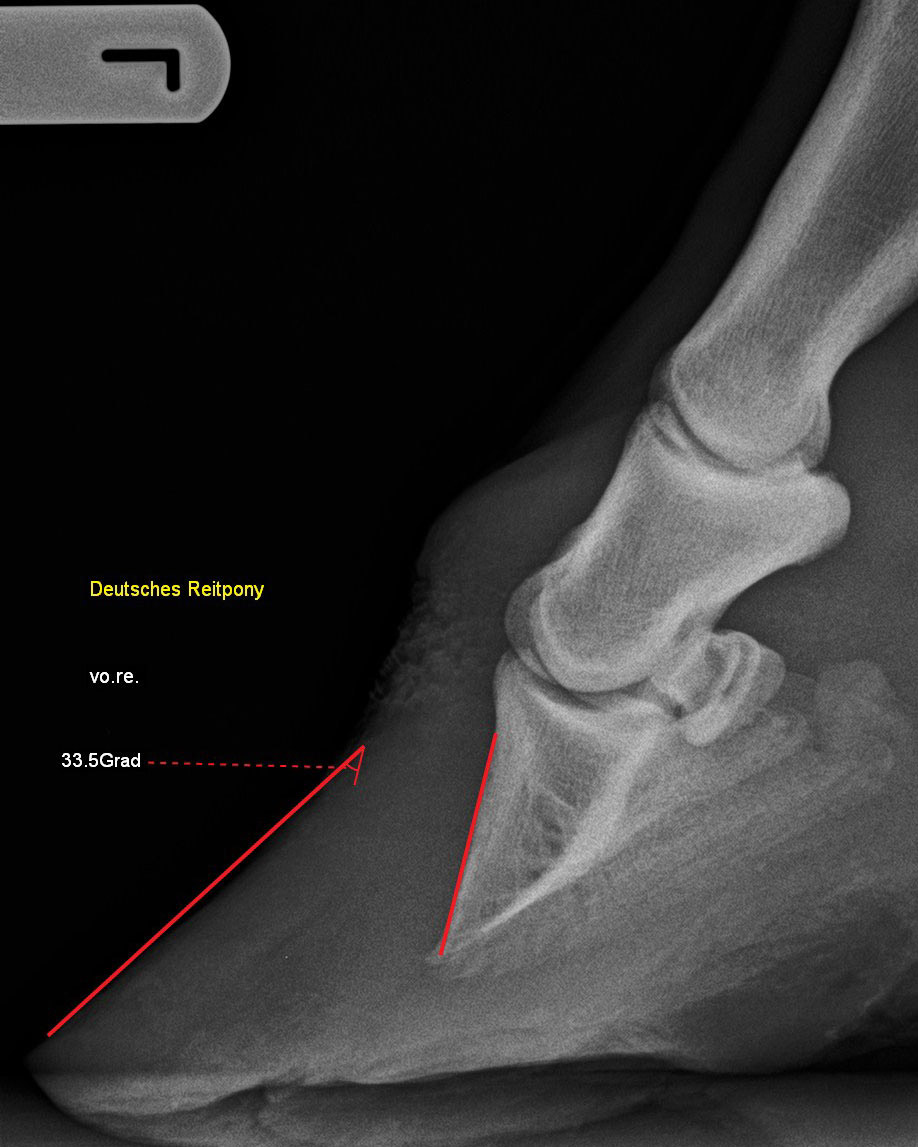

Kleinpferd mit Hufrehe - Hufbeinrotation 33,5°